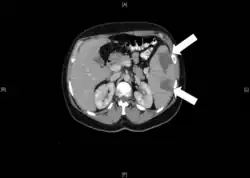

Инфа́ркт (лат. infarcire «начинять, набивать») — омертвление (некроз) органа или ткани вследствие острого недостатка кровоснабжения[1][2]. Причины инфаркта: тромбоз, эмболия, длительный спазм артерий и функциональное перенапряжение органа в условиях гипоксии[1].

Виды инфаркта по форме[1]:

- Клиновидная форма. Специфична для селезёнки, почки, лёгкого.

- Неправильной формы. Встречается в сердце, и головном мозге (ишемический инсульт, инфаркт таламуса).

По цвету[1]:

- Белый — встречается в селезёнке и головном мозге.

- Белый с геморрагическим венчиком — в сердце и почках.

- Красного цвета, пропитанный кровью — в лёгком на фоне хронического венозного полнокровия.